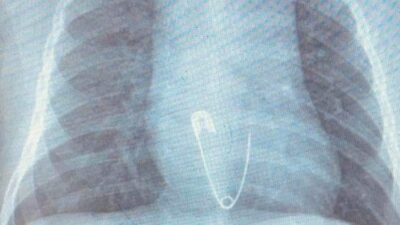

5 aylık bebeğin yuttuğu çengelli iğne soluk borusuna saplandı!